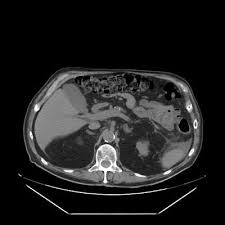

L'ascite est une accumulation anormale de liquide dans l'enveloppe de l'abdomen. Cette accumulation est due à la cirrhose, dans près de 80% des cas. L'ascite est indolore et n'est diagnostiquée que lorsque l'on observe une augmentation du volume de l'abdomen, une prise de poids et une lourdeur abdominale dues à l'accumulation de liquide.